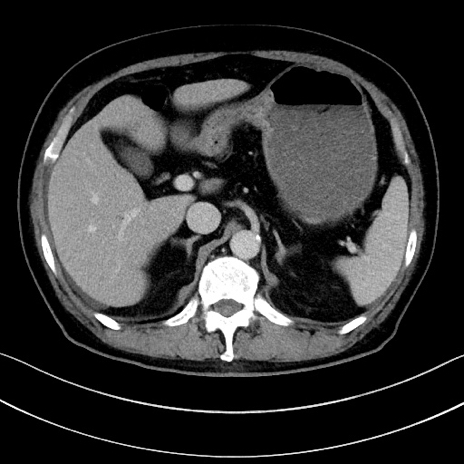

冠状断像

【症例】70歳代男性

【主訴】腹痛

【現病歴】今朝から腹痛あり。全体的に痛い。特に左上の方。排ガスが今日はない。冷や汗が出る。

【既往歴】直腸癌術後

【身体所見】左側腹部〜上腹部に圧痛あり。腹膜刺激症状明らかなではない。軽度反跳痛。左下腹部に術後瘢痕あり。

【データ】WBC 7700、CRP 0.02